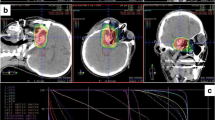

Patients were immobilized using a thermoplastic head mask system. All patients received computed tomography (3-mm slice thickness) for three-dimensional treatment planning. For exact contouring of the treatment volume and organs at risk, a three-dimensional correlation with contrast-enhanced T1-weighted and T2-weighted (T2-STIR) magnetic resonance imaging (MRI) was performed, which was then rigidly registered on the CT scan. All patients had macroscopic residual disease. Compression of the brainstem was present in 38%, contact without compression in 18%, and no contact but less than 3 mm distance in 16%.

For the boost clinical target volume (CTV2), a margin of 1–2 mm was applied to the gross tumor volume (GTV). The primary clinical target volume (CTV1) contained CTV2 and the preoperative tumor extent. Both PTVs (PTV1 and PTV2) were formed by adding a safety margin of 3 mm to the corresponding CTV. The Siemens Syngo PT Planning software (Siemens Healthineers, Erlangen, Germany) was used for treatment planning. The treatment was performed at the HIT in Heidelberg, Germany, using protons and carbon ions in active raster scan technique. Dose distribution was calculated using the local effect model 2 (LEM2). Dose constraints to OARs were prescribed according to the QUANTEC database, particularly the brainstem was limited to a maximal dose of 59 Gy (RBE; EQD2) [16]. If dose prescription goals and dose constraints could not be met at the same time, underdosage of the target was preferred. Detailed information concerning carbon ion treatment has been published previously [17].

A total of 111 patients received carbon ion treatment (C12) with a median total dose of 66 Gy (RBE; 45 Gy to PTV1, 21 Gy to PTV2) in a fractional dose of 3 Gy (RBE) six times per week (treatment on Saturdays). The remaining 36 patients received proton treatment (H1) with a median total dose of 74 Gy (RBE; 50 Gy to PTV1 and 24 Gy to PTV2) in 2‑Gy (RBE) fractional doses six times per week. If the total median dose of hypofractionated carbon ion therapy is calculated in EQD2 with an alpha/beta value of 10, the total dose is 71.5 Gy, and thus comparable to the proton dose of 74 Gy (RBE).

The treatment of skull base chordoma is particularly difficult because of the proximity to a number of organs at risk. Especially relevant are the optic system, with visual impairments as a side effect, and the brainstem as the center of vital functions, which need to be preserved at all cost. Depending on the proximity of the tumor to these organs, especially the brainstem, a local underdosage of the tumor with a possibly higher risk of recurrence has to be accepted, probably resulting in inferior local control. Increasing evidence for this suggestion has emerged in recent years. For example, Takagi et al. reported on 24 patients treated with protons or carbon ions and observed a marked reduction in 5‑year local control (81% vs. 100%) in patients with close proximity of tumor and brainstem, although this difference was not statistically significant. Guan et al. reported on 91 patients with skull base or cervical chordomas treated with protons, carbon ions, or combinations of both, and observed significantly reduced LC, PFS, and OS in patients with compression of brainstem or the optic apparatus [32]. Weber et al. found worse local control and overall survival in a mixed cohort of skull base chordomas and chondrosarcomas if tumor compressed the brainstem or optic apparatus [29] and Iannalfi et al. reported similar results in their prospective trial using protons or carbon ions for skull base chordomas [27]. These findings are augmented by a recent analysis of Basler et al., who saw the majority of recurrences in the area of the brainstem in a mixed collective of chordoma and chondrosarcoma and were able to show a compromised dose distribution in those areas in their dosimetric analysis [33].

In our cohort, we strictly applied our predefined dose constraints especially for brainstem (59 Gy EQD2 based on the QUANTEC data), accepting possible target volume dose restrictions. Consistently, we found significantly inferior local control and a trend toward inferior survival in patients with tumors located less than 3 mm from the brainstem, if treated in a primary situation. Surprisingly, no marked differences were observed in patients treated in a recurrent situation, although this might be driven simply by the much smaller sample size of recurrent cases.